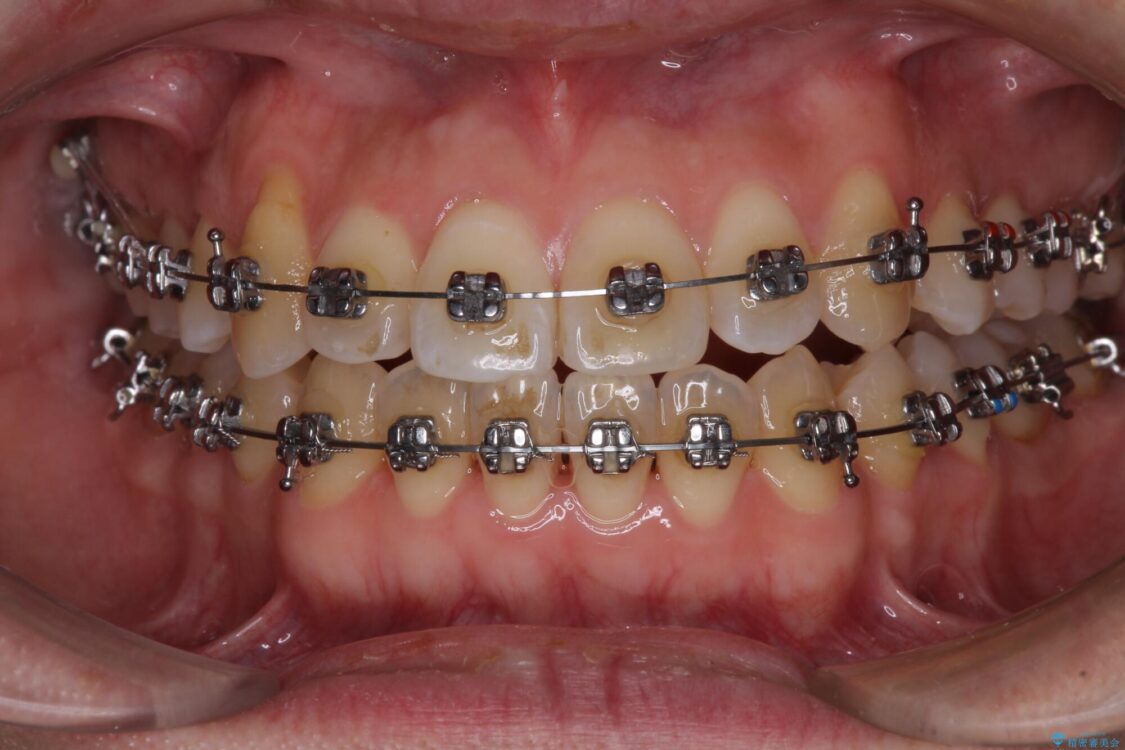

治療途中

• 左右の八重歯が気になる ワイヤー装置での咬み合わせ改善 治療途中画像